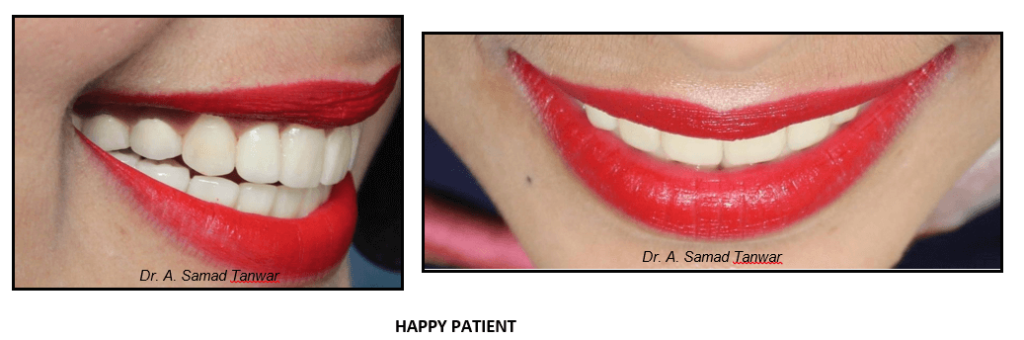

Immediately after post insertion

Occlusal view of the restorations In-situ

Restoration of aesthetic and function by using blend of conventional and minimally invasive